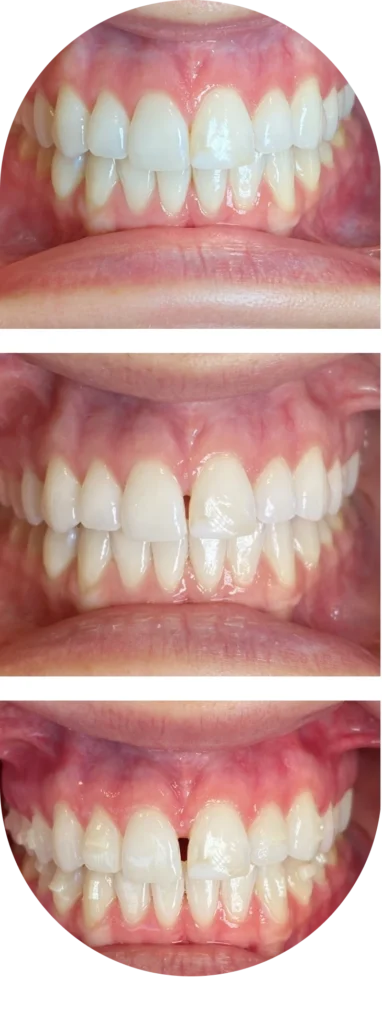

Dr. Green guides slow, controlled activation to widen the maxilla without creating a large gap.

Simultaneous Invisalign

Avoid a visible gap in the front teeth and optimize alignment for perfect smile at the same time!

This is a common concern. Dr. Green uses a no-gap protocol to carefully control expansion. When appropriate, Invisalign is incorporated during treatment to help minimize or avoid visible spacing between the front teeth.